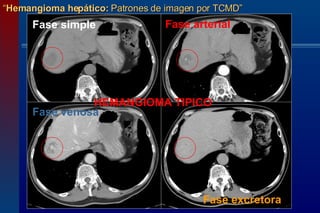

“ Hemangioma hepático:  Patrones de imagen por TCMD” Imágenes de TC en fases simple, arterial, venosa y excretora demostrándose las características típicas del hemangioma. Fase simple  Fase arterial  Fase venosa  Fase  excretora

El  patrón típico por TCMD del hemangioma hepático es el de lesión de dimensiones igual o <4 cms, que se caracteriza  en fase simple por ser hipodensa, con hipoatenuación similar a la de los vasos,  en fase simple, de contornos definidos, subcapsular.  En el transcurso del examen dinámico postcontraste IV, muestra un reforzamiento inmediato, periférico, nodular, discontinuo, con llenado  centrípeto (de la periferia al centro), hiperdenso en fase arterial con reforzamiento similar al alcanzado por la aorta o vasos sanguíneos contiguos,  para hacerse isodenso al parénquima hepático en fases tardías (2,4). “ Hemangioma hepático:  Patrones de imagen por TCMD” HEMANGIOMA HEPATICO

Hipodenso  en fase simple “ Hemangioma hepático:  Patrones de imagen por TCMD” Reforzamiento periférico  nodular  discontinuo  en fase arterial Isodenso,  con llenado centrípeto  en fase venosa Isodenso  en fase tardia Fase simple  Fase arterial  Fase venosa  Fase excretora